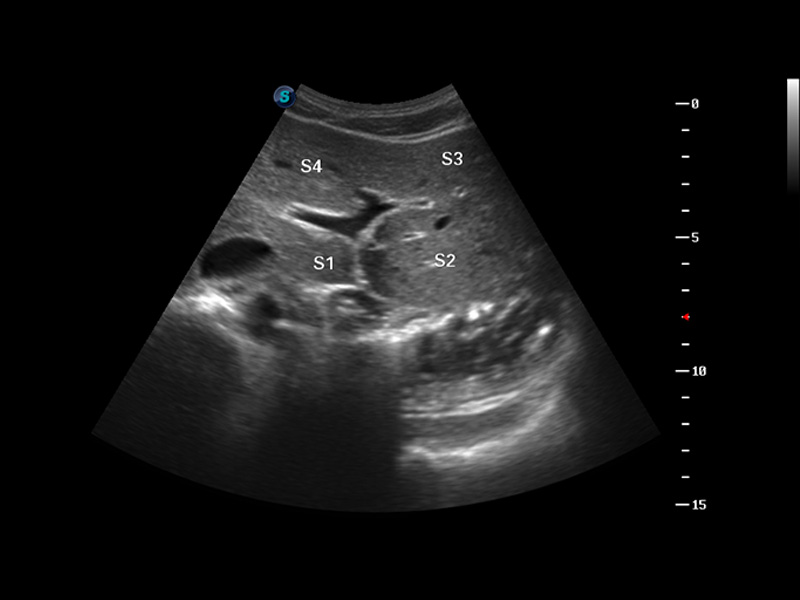

S8 EXP便携式彩色多普勒超声诊断仪是银河集团官网研发的高端全身应用型便携彩超。高通道的VIS平台融合可视化(Visual)、智能化(Intelligent)和人性化(Smart)的特点,配以银河集团官网自主研发生产的探头大家族,使您能够快速、准确的获得病人信息,提高工作效率的同时减轻疲劳。

μ-Scan微米成像

谐波成像

实时宽景成像

空间复合成像

3D/4D成像